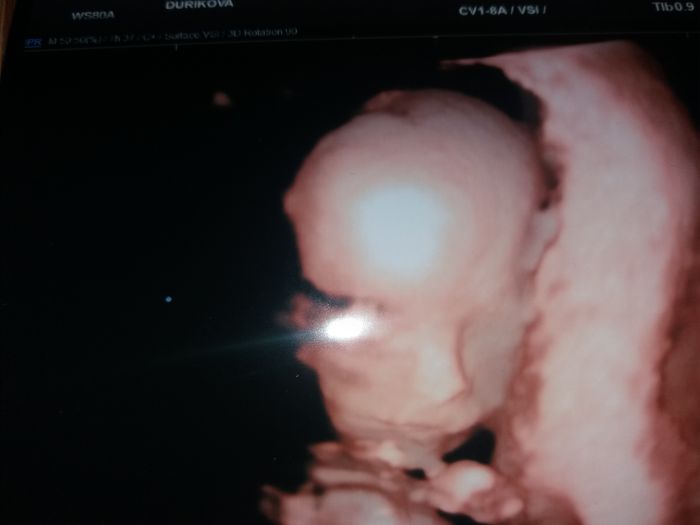

zatím nevím, snad už ten příští týden budu vědět.. dělal mi dnes ultz spodem a jediné co mi řekl, že mám něčeho na rozdávání ale nějak jsem přeslechla čeho

Jj a u toho ultz mi mimi ani neukázal, jen se sám na 10 vteřin podíval a tot vše

[1085449] jj Pajko, taky se divím, že mi dělal ultz spodkem, čípek vpořádku. Naposledy jsem miminko viděla ve12tt na prvním screeningu.